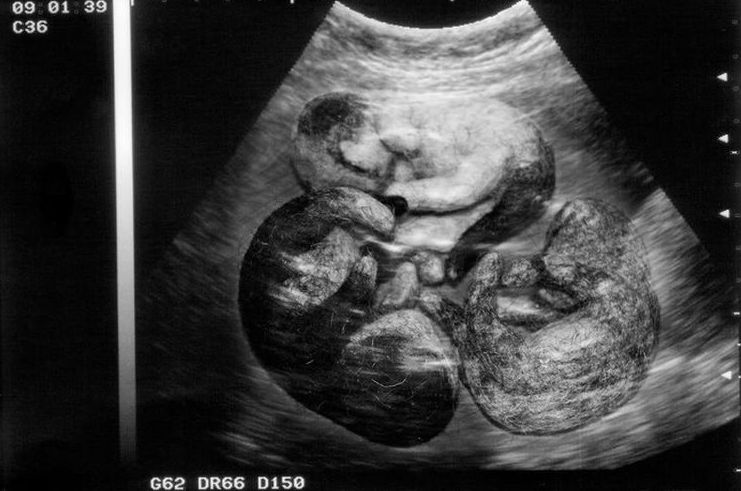

- 21e jour – L’embryon atteint 5 mm et le cœur commence à se développer. La grossesse peut désormais être confirmée par échographie : les embryons sont encore indiscernables, mais leurs membranes fœtales sont visibles.

- Le 22, une échographie peut être réalisée pour confirmer la grossesse. Durant cette période, des pertes vaginales claires, une perte d'appétit, des vomissements et de la léthargie peuvent survenir.

- 23-24 – Le futur fœtus mesure près d'un centimètre et ses yeux, son nez, ses oreilles, ses mâchoires et son foie commencent à se former. Ces jours sont considérés comme idéaux pour une échographie.

- Du 27 au 29 – C’est le moment idéal pour diagnostiquer une grossesse, par échographie et palpation abdominale, car les fœtus ont déjà atteint près de 1,7 cm. Leurs crânes et leurs mâchoires commencent à se calcifier.

- 52-54 – L’abdomen continue de grossir et l’animal passe le plus clair de son temps à se reposer et à faire sa toilette. Les radiographies permettent désormais de déterminer le nombre de fœtus.